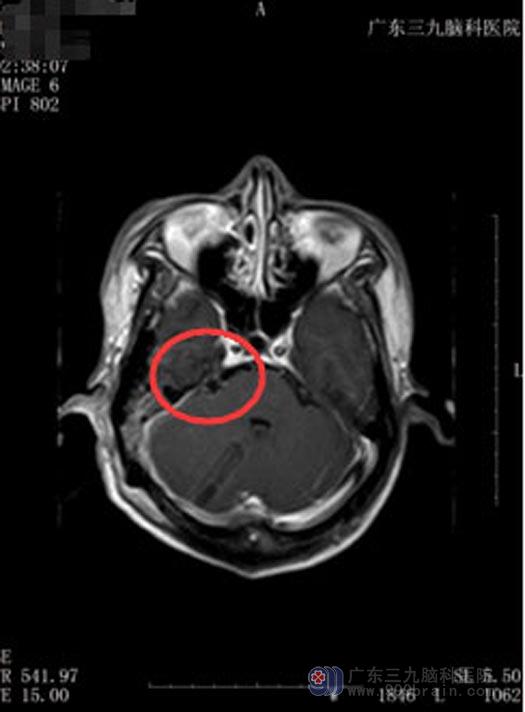

可曾大叔的听神经瘤却没有按常规出牌。55岁的他经常会莫名其妙地阵发性头痛,休息后能够缓解。有一天送孙子去幼儿园,回家后突然四肢抽搐,口吐白沫,意识消失,持续几分钟后才醒过来。吓坏了的老伴赶紧陪着他一起来到广东三九脑科医院综合神经外科,头颅MR检查提示“右桥小脑角区占位”。

![曾汝早术前MPN}G}Y]VHH9YL6XM1]936D.jpg](/upload/news/NewsContent/2018/2018-09/20189291557508.jpg)